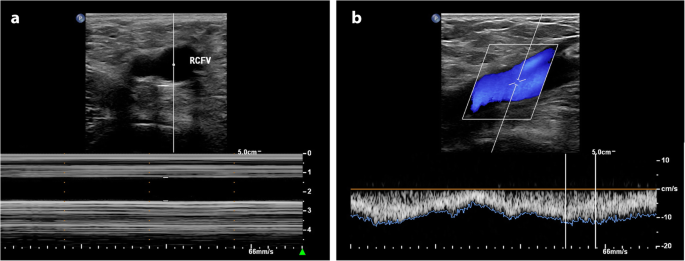

Parturients were instructed to fast for at least 6 h before the cesarean surgery. The ultrasound measurements were performed with the parturient on the transfer bed in the post-anesthesia care unit 15 min before anesthesia. An ultrasound device (EPIQ7; Philips, Ultrasound, Bothell, WA, USA) with a high-frequency linear array probe (L12–5; 5–12 MHz) was used for the measurement of the transverse diameter and peak velocity of the RCFV (Fig. 1). A cardiac probe (SC-1; 5–1 MHz) was used to measure the anteroposterior diameter and peak velocity of the IVC (Fig. 1). Parturients were in a supine position when the ultrasound examination was performed. Measurement sequences for the transverse diameter of the RCFV, peak velocity of the RCFV, anteroposterior diameter of the IVC, peak velocity of the IVC were always applied to ensure that all examinations were completed within 15 min. The transverse diameters and peak velocities of the RCFV were measured 1 cm proximal to the confluence of the great saphenous vein into the common femoral vein during end expiration (Fig. 1). The cardiac probe was placed below the xiphoid. The anteroposterior diameters and peak velocities of the IVC were measured 2–3 cm below the IVC-right atrial junction during end expiration (Fig. 2). Transverse and anteroposterior diameters were measured by M-mode ultrasound, and the M-mode sample line was always adjusted to pass through the center of vessels to measure the diameters more precisely (Fig. 1a and Fig. 2a). All peak velocities were measured using the pulsed-wave Doppler ultrasound mode. The Doppler sampling volume was placed in the center of the blood vessel, and the width of the sampling range gate was 2 mm. Doppler angle correction was performed when measuring velocity, with the calibration main line parallel to the direction of blood flow and at an angle of 50–60° (Fig. 1b and Fig. 2b). All the ultrasound recordings were performed by a board-certified ultrasound specialist; the anesthesiologists and parturients were blinded to the examination results.

There were two highlights of the ultrasound measurements in this study. First, M-mode ultrasound was used to measure the diameters of the RCFV and IVC. Although B-mode ultrasound is more commonly used for the measurement of vessel diameters, M-mode can display the diameter of vessels at different respiratory phases. In this study, all the diameters of IVC and RCFV were measured during end expiration to eliminate the influence of respiration. Second, we focused on the overall impact of IVC compression on the lower extremity venous system, including both the femoral and saphenous veins. Hence, the measurement site of RCFV was 1 cm proximal to the confluence of the great saphenous vein into the common femoral vein rather than the commonly used measurement site (immediately distal to the confluence of the great saphenous vein into the femoral vein).